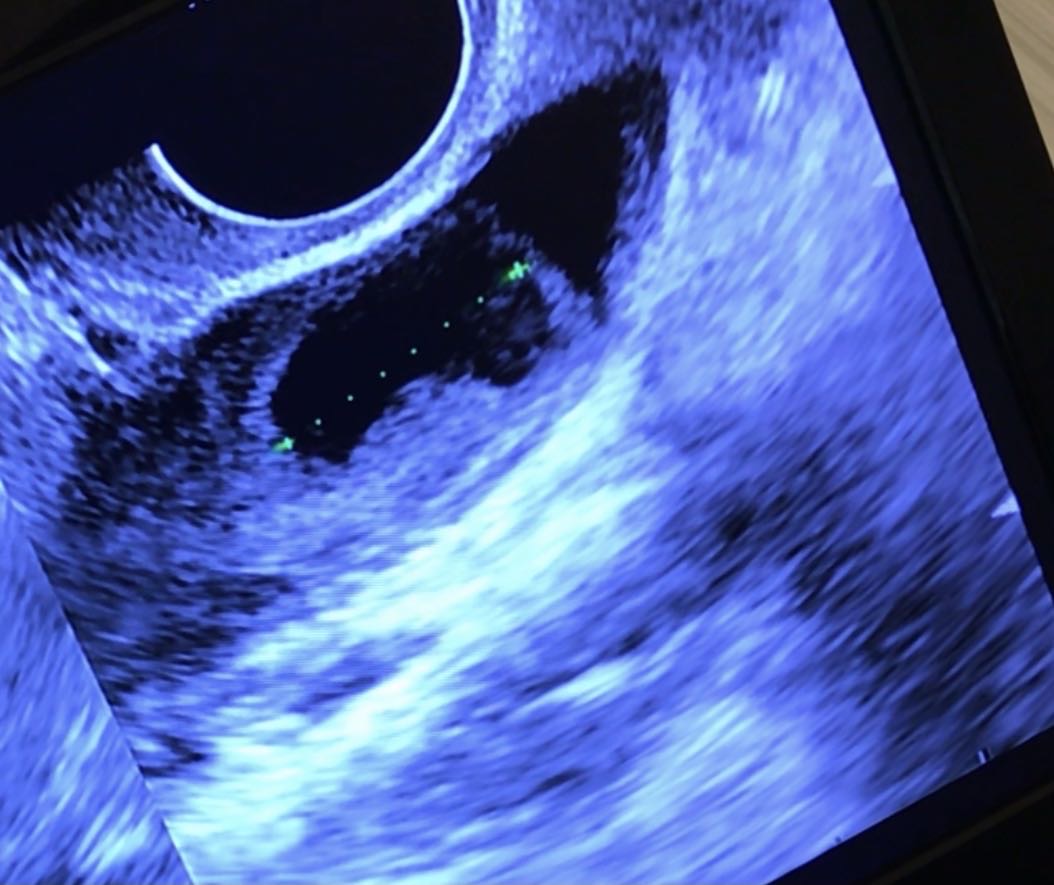

这个月没促排,b超监测说是卵泡已排,内膜10.1毫米,为什么卵泡没有消失还有17毫米留在那里?已上传照片,这是排了吗?另外,排了卵可以吃补佳乐和地屈孕酮吗?排卵后吃补佳乐主要是干什么的?

排卵后卵泡液不会马上消失,如果定期监测,卵泡突然减小就是排了,补佳乐和地屈孕酮都是保胎用的,调理子宫内膜的,遵医嘱用药就行了!